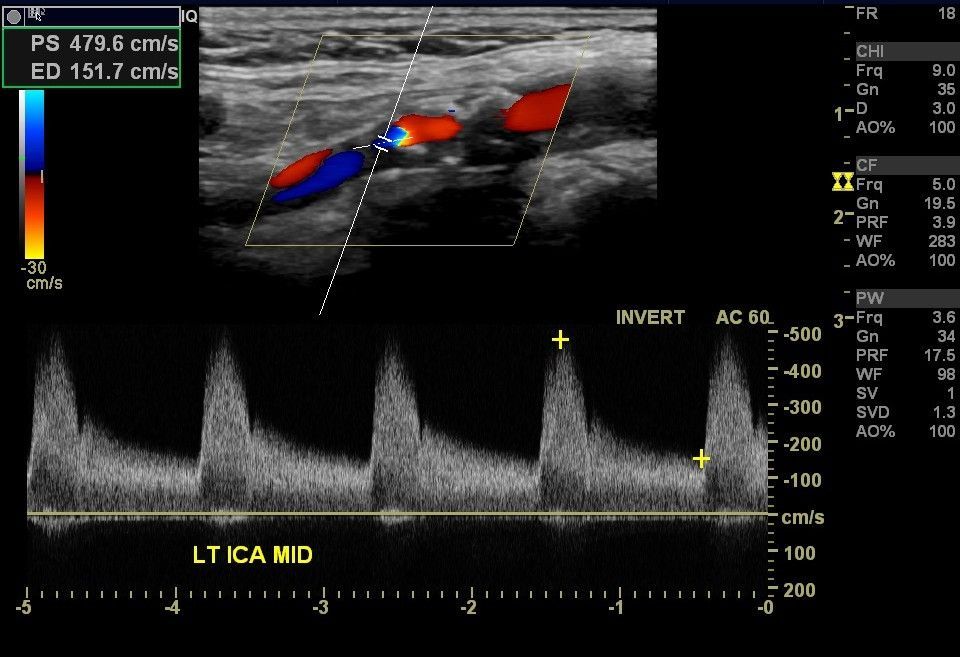

Ultraschall der Hirnversorgenden Gefäße

Mit einer sog. Duplex-Sonographie der hirnversorgenden, großen Gefäße kann man feststellen, ob die Durchblutung des Gehirns ausreichend ist oder ob es Verengungen (Stenosen) dieser Gefäße gibt. Dies ist in der Diagnostik des Schlaganfalls sehr wichtig, aber kann auch wichtige Hinweise geben bei der Ursachensuche z.B. sog. Synkopen.